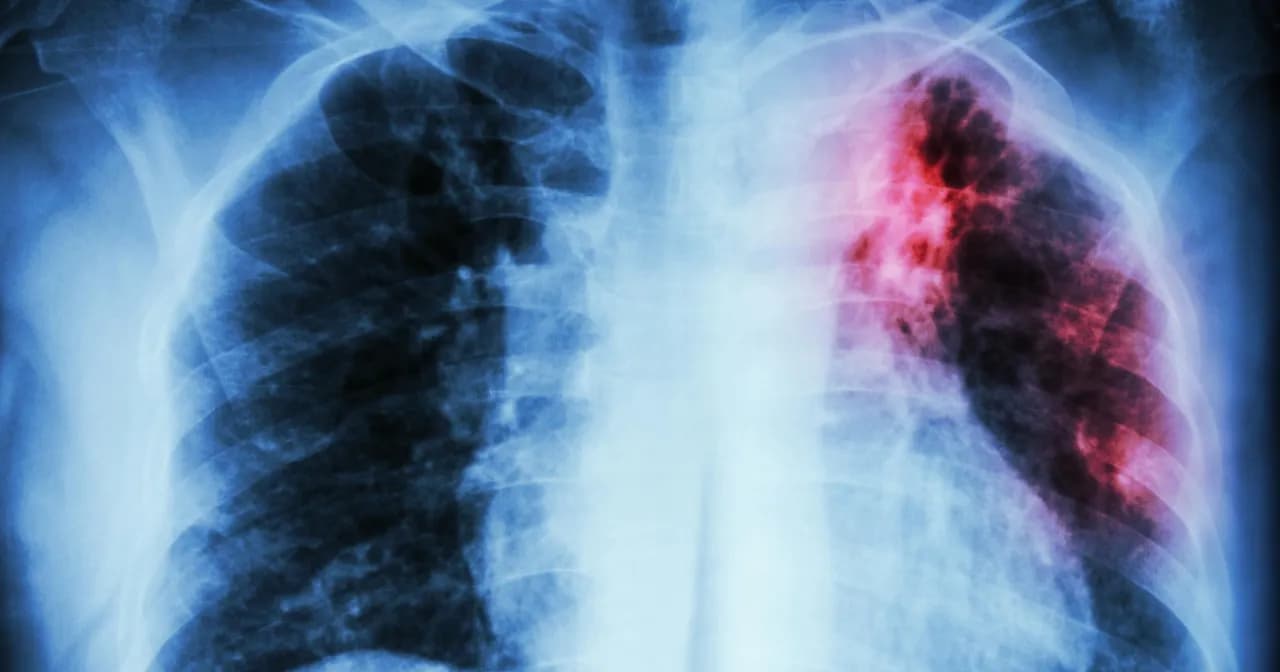

Poznaj najważniejsze objawy gruźlicy, które pomogą w szybkim rozpoznaniu choroby. Dowiedz się, jakie są charakterystyczne symptomy gruźlicy płuc i pozapłucnej oraz kiedy zgłosić się do lekarza.